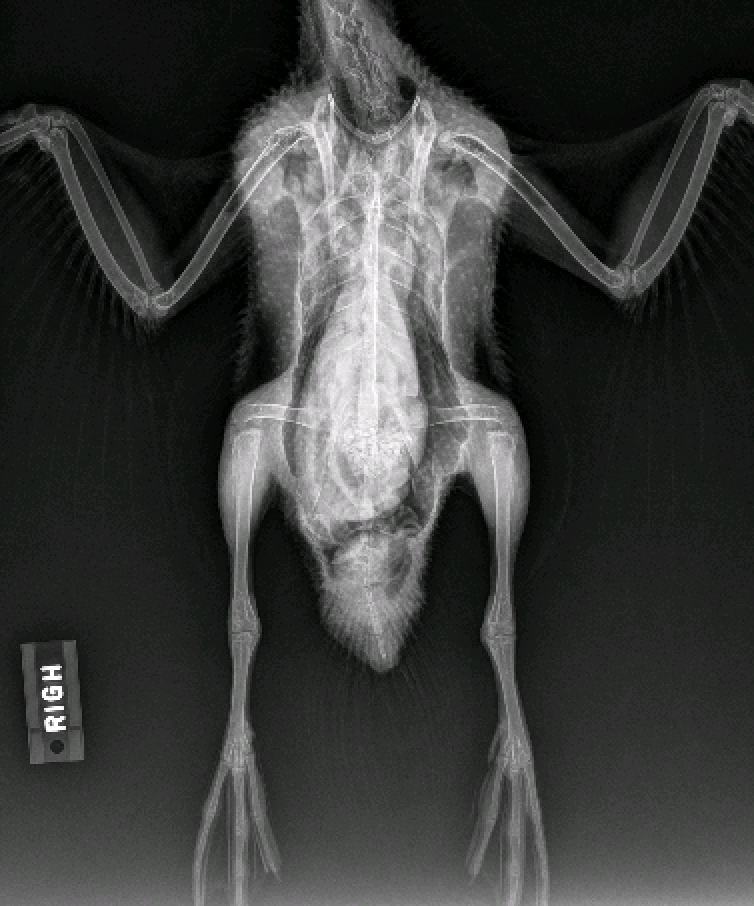

Since the patient was still having trouble walking and there was concern about the lesions on her feet, a plan was made to take radiographs. The patient was sedated and put under anesthesia to take the radiographs, which showed evidence of hind-end trauma. The pelvis appeared to have several fractures but in non-weight bearing portions and therefore was not a cause for concern. There was also an abnormality in the synsacrum, a fusion of the spine and pelvis found in avian species, which could beĀ causing inflammation and spinal problems. However, the issues noted on the radiographs did not seem to be recent, and the plan was to continue treatment with anti-inflammatory medication and provide increased swim time while monitoring for signs of improvement.